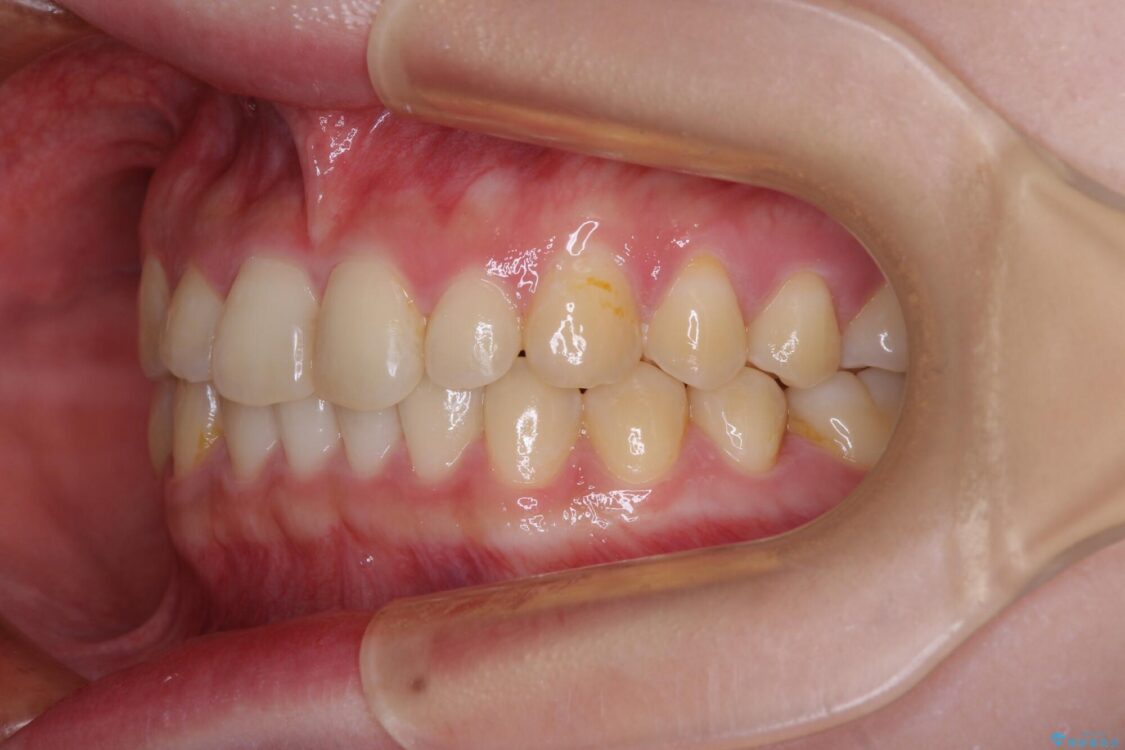

根管治療を行ったままの奥歯と、矯正治療の後戻りを気にして来院された患者様です。

治療前

• 治療途中の奥歯と矯正治療の後戻り インビザライン・ライトによる矯正治療 治療前画像